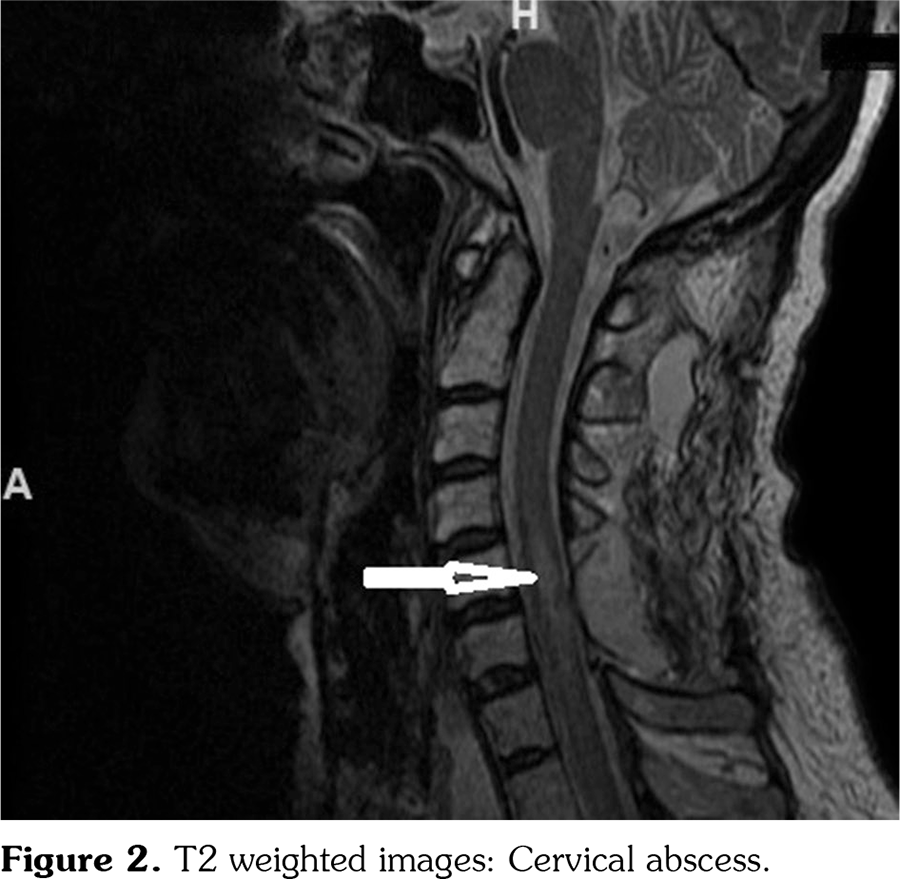

Seven days after the surgery, her symptoms worsened and she also developed arm weakness. Cervical MRI revealed an intramedullary mass between the C5-C7 vertebra levels which was consistent with an abscess (Figure 2) although the CRP levels were within the normal range. She was re-operated and the intradural abscess was drained. The culture of pus from the abscess turned out to be negative. She developed severe pneumonia. The blood culture was negative. One month after the first surgery, Candida albicans was observed in the culture of sputum in the intensive care unit and patient died despite the antifungal treatment.